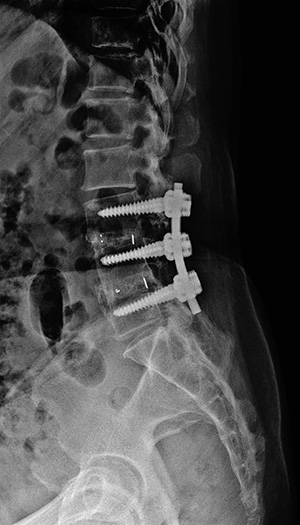

▼ 척추뼈 2개를 묶은 유합술 ▼

• 유합술 전면 X-ray

• 유합술 측면 X-ray

▼ 척추뼈 3개를 묶은 유합술 ▼